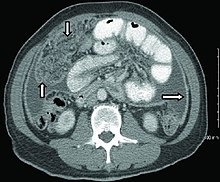

Extrapulmonary tuberculosis[edit | edit source]

CT scan of peritoneal tuberculosis, a form of extrapulmonary tuberculosis. The omentum and peritoneal surfaces are thickened (arrows).[4]

Peritoneal tuberculosis may mimic peritoneal carcinomatosis on CT scan.[4]